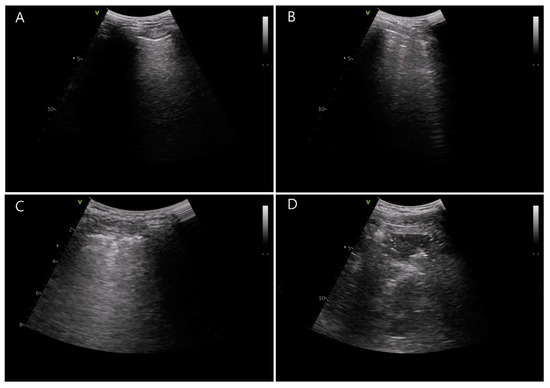

- Acosta, C.M.; Maidana, G.A.; Jacovitti, D.; Belaunzarán, A.; Cereceda, S.; Rae, E.; Molina, A.; Gonorazky, S.; Bohm, S.H.; Tusman, G. Accuracy of Transthoracic Lung Ultrasound for Diagnosing Anesthesia-induced Atelectasis in Children. Anesthesiology 2014, 120, 1370–1379. [Google Scholar] [CrossRef] [PubMed]

- Monastesse, A.; Girard, F.; Massicotte, N.; Chartrand-Lefebvre, C.; Girard, M. Lung Ultrasonography for the Assessment of Perioperative Atelectasis. Anesth. Analg. 2017, 124, 494–504. [Google Scholar] [CrossRef] [PubMed]

- Volpicelli, G.; International Liaison Committee on Lung Ultrasound (ILC-LUS) for the International Consensus Conference on Lung Ultrasound (ICC-LUS); Elbarbary, M.; Blaivas, M.; Lichtenstein, D.A.; Mathis, G.; Kirkpatrick, A.W.; Melniker, L.; Gargani, L.; Noble, V.E.; et al. International evidence-based recommendations for point-of-care lung ultrasound. Intensive Care Med. 2012, 38, 577–591. [Google Scholar] [CrossRef]

| Lung ultrasound score | ||||

| Preoperative baseline | 6.0 (4.0–11.0) | 4.5 (3.0–9.0) | 0.143 | −1.0 (−4.0 to 0.0) |

| After extubation | 8.1 ± 5.7 | 12.2 ± 4.2 | 0.002 | −4.13 (−6.74 to –1.53) |

| Difference | −0.5 ± 2.7 | 6.0 ± 2.9 | <0.001 | −6.53 (−8.00 to –5.07) |